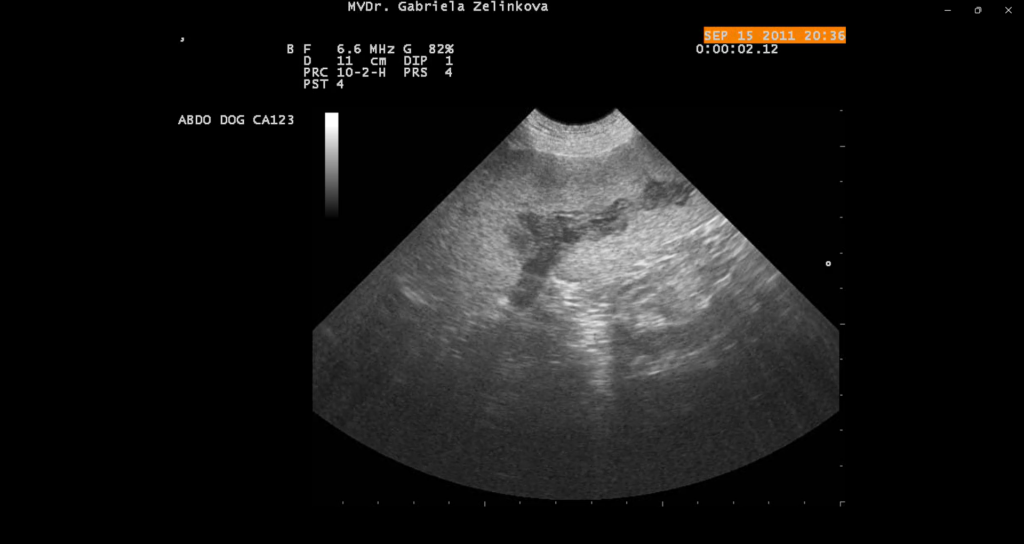

Tromboembolie sleziny

Akutní tromboembolická okluze a.lienalis s globální ischemickou reakcí parenchymu.